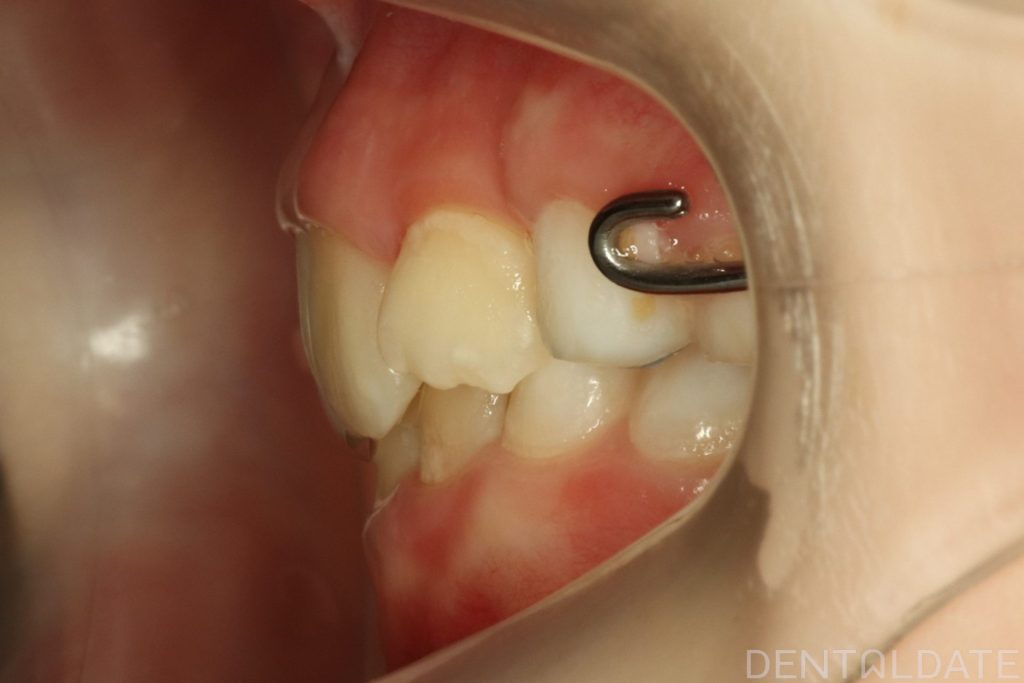

The patient had been undergoing orthodontic treatment at another clinic for 1.5 years with no significant progress.

With a new treatment plan in place -the anterior bite was normalized within just one week.

We are now focused on final adjustments to tooth alignment and occlusal height.